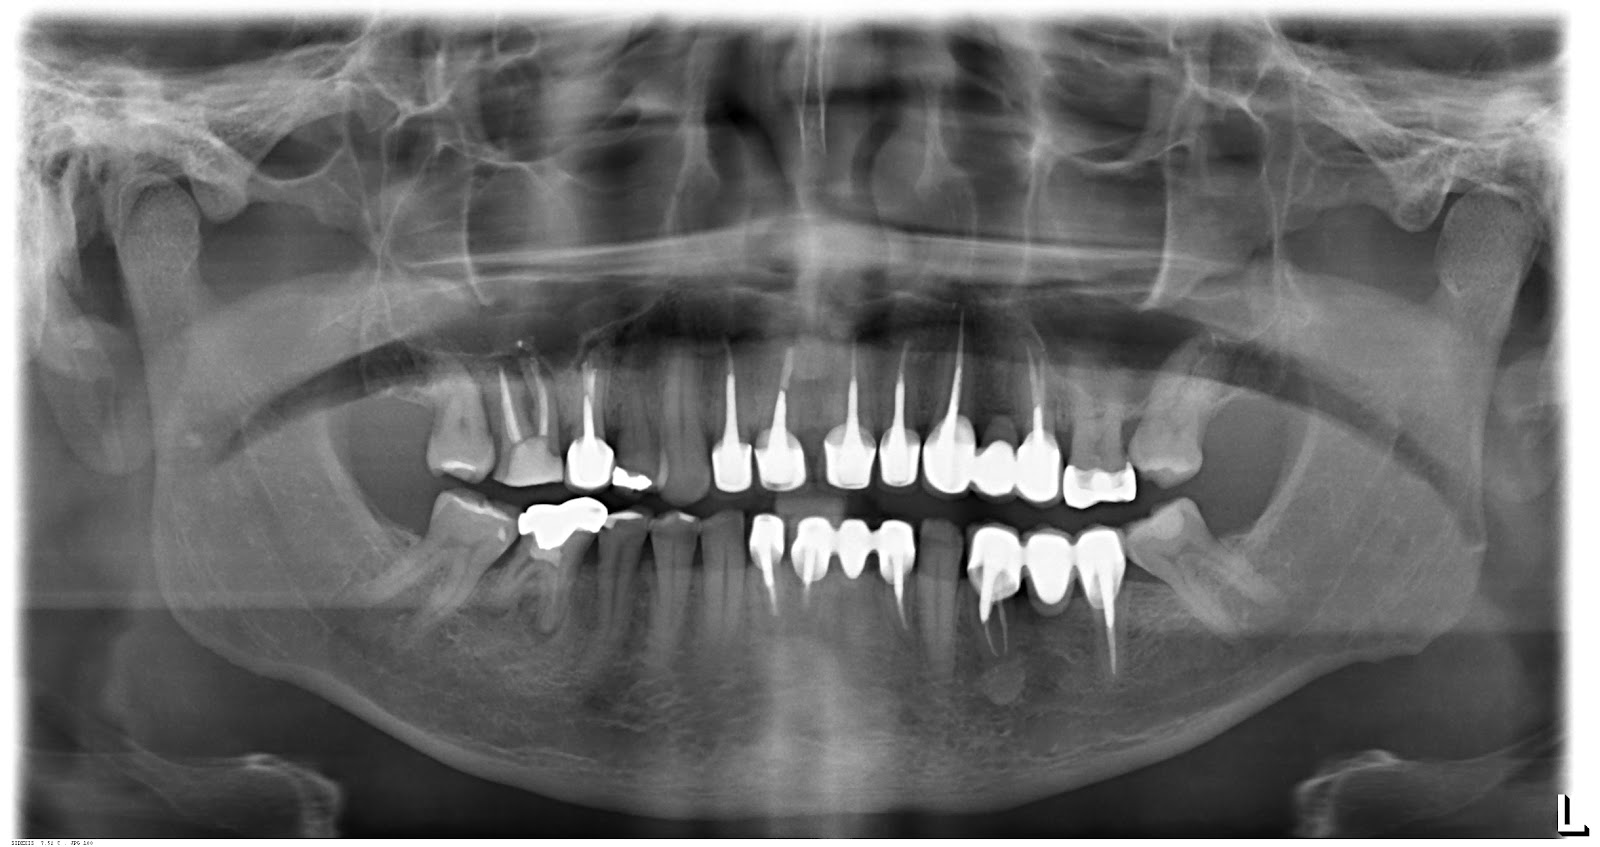

Entendendo a Radiografia Panorâmica. Diferente do raio-x convencional, que foca em áreas específicas e isoladas, a radiografia panorâmica abrange uma visão completa da região facial. "Este exame gera uma imagem tomográfica de alta precisão, englobando arcada dentária, maxilar e mandíbula, facilitando imensamente a análise e o.. Radiografia panorâmica uma das técnicas radiográficas mais solicitadas e difundidas em todas as especialidades da Odontologia. Ela se trata de um raio-x sobre o complexo maxilo-mandibular. Esse tipo de radiografia possibilita ao cirurgião-dentista a visualização dos elementos dentais, mesmo os que ainda não estão erupcionados, bem como.

A radiografia panorâmica dental é um exame muito comum na odontologia, fazendo com que o dentista tenha uma visão total e detalhada da estrutura oral de um paciente. Esta técnica melhorou o diagnóstico e o plano de tratamentos dentários, fazendo com que os profissionais realizem uma análise precisa de toda a região oral em uma imagem.. O que é radiografia panorâmica? A radiografia ou raio X é um exame que usa radiação em baixa quantidade para obter imagens internas do corpo. Ela foi desenvolvida no ano de 1895, pelo alemão Wilhelm Conrad Röntgen. Esse exame é utilizado para identificar possíveis fraturas e tumores no corpo.